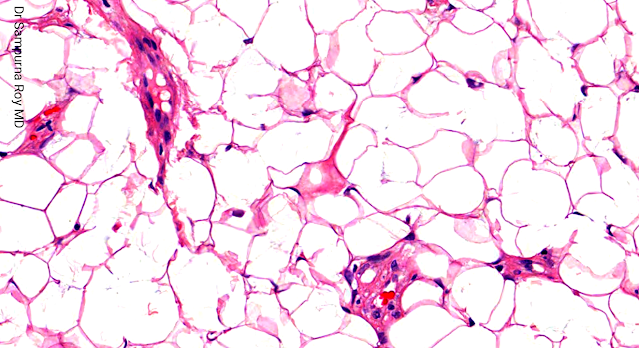

Dermatopathology Case 193 Get link Facebook X Pinterest Email Other Apps April 08, 2022 A 28 year old male with a subcutaneous lesion on the left forearm. Answer Get link Facebook X Pinterest Email Other Apps Comments